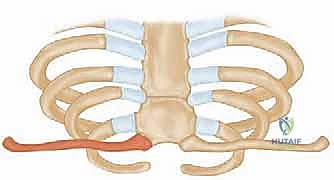

لا يمكن ببساطة خياطة الأربطة الممزقة لضمان الاستقرار. لذلك، يستخدم الدكتور هطيف تقنية متقدمة لإعادة البناء باستخدام "رقعة وترية" (Tendon Graft).

* أخذ الرقعة: غالباً ما تؤخذ من وتر العضلة الرشيقة (Gracilis) أو العضلة نصف الوترية (Semitendinosus) من ركبة المريض نفسه (Autograft)، أو استخدام رقعة صناعية طبية عالية الجودة.

* حفر الأنفاق العظمية: يتم حفر ثقوب دقيقة جداً في عظم الترقوة وعظم القص باستخدام أدوات جراحية متطورة.

5. تمرير الرقعة وتثبيتها (تقنية الرقم 8)

يتم تمرير الرقعة الوترية عبر الثقوب العظمية بنمط يشبه الرقم 8 (Figure-of-eight). هذه التقنية الميكانيكية الحيوية توفر قوة استقرار هائلة تحاكي قوة الأربطة الطبيعية (الرباط الكبسولي والرباط الضلعي الترقوي).